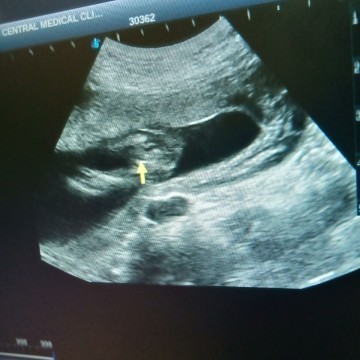

แม่ๆ มองเป็นเพศ หญิง หรือ เพศชายค่ะ ☺️

ผญ ค่ะแม่บ้านนี้ผู้ชาย เห็นไข่เห็นจู๋ชัดเลย

น่าจะผญ.นะคะ คุณหมอคงบอกแม่แล้วว่าเพศอะไร

ผู้หญิงค่ะ ถ้าผู้ชายน่าจะโด่แบบบ้านนี้ 😂

เป็นกลีบมาเลย🥰🥰🥰หญิงค่ะ

ญ จร่าแม่กลีบๆนะเราว่า

น่าจะผ.ญ ค่ะ

น่าจะหญิงค่ะ

บ้านนึ้ ช

ญ.ป่าวคะ